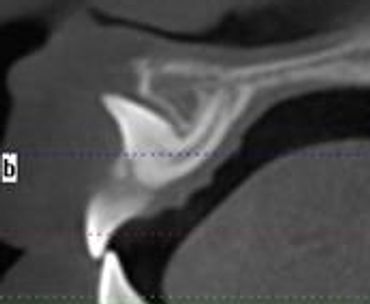

We also utilize the most prestigious Oral and Maxillofacial Radiologist in its field. Services offered for Radiographic Diagnostic Reporting include but not limited to: Implant Work-up, TMJ, Impaction/Localization study, Tissue Pathology, Airway and Sinus Evaluation.

This one scan provides more images than plain film conventional imaging, with complete visualization of the patient's entire maxillofacial region. These images clearly display TM disorders, impacted teeth, critical bone and tooth relationships, oral- nasal airways, para-nasal sinus, mandibular canal and difficult to see pathologies within one volume. The user friendly software system reconstructs true size, distortion free, high resolution images.